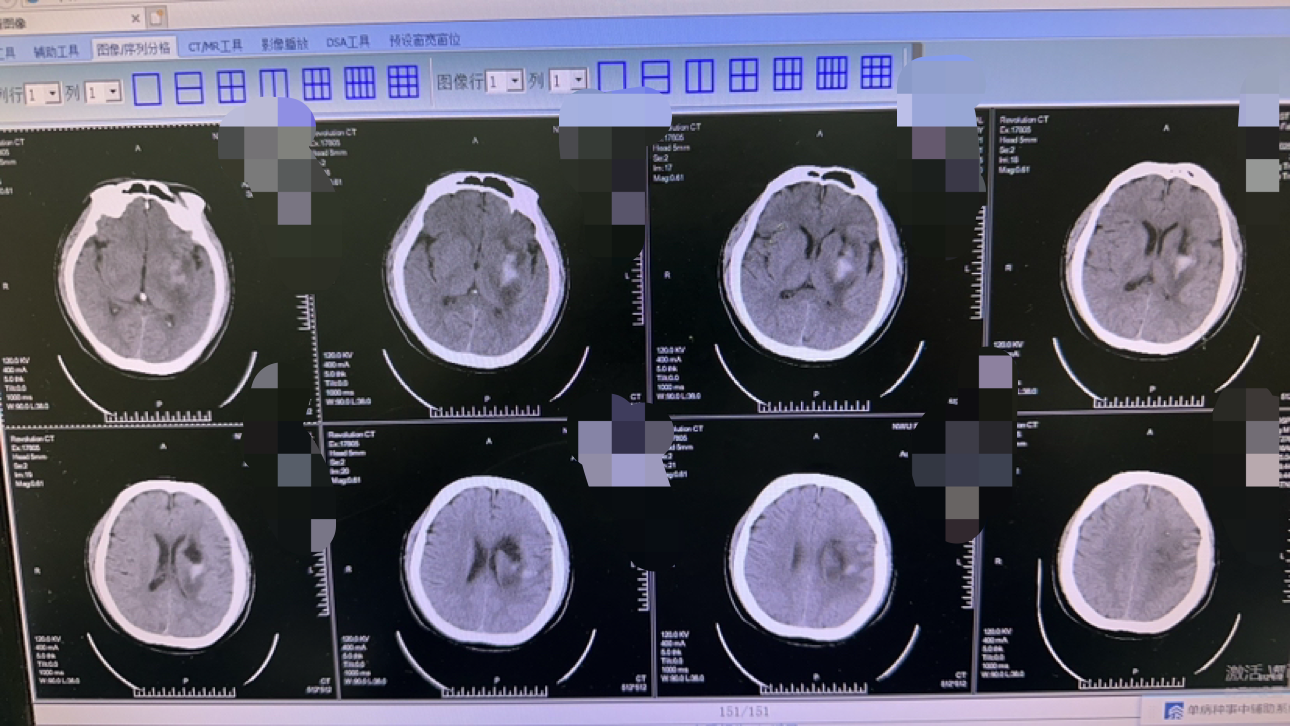

毫米级精度:机器人系统实现亚毫米级血肿定位,减少脑组织损伤。

极速微创手术:0.5cm切口,0.3cm骨孔,10分钟手术,2ml出血量。

对比传统术式:更小的创伤,更低的风险,更快的恢复,97%成功率,10天平均住院时间,50%费用降低。